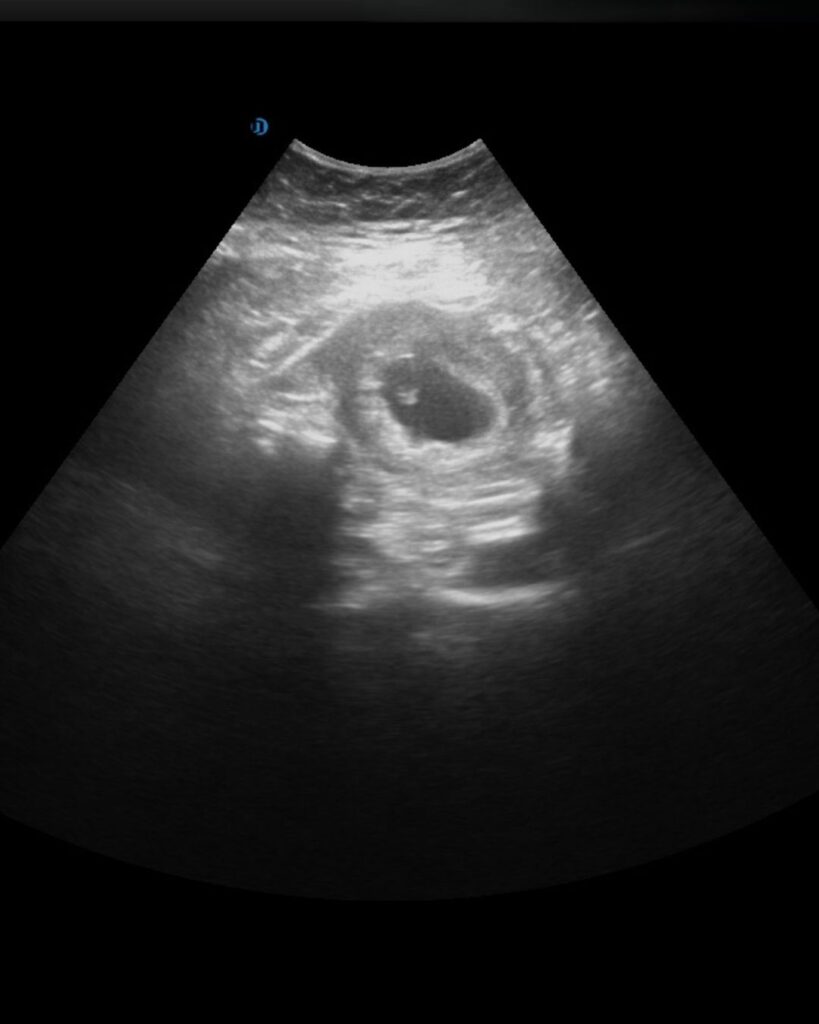

Eerste ontwikkeling

11-14 weken zwangerschap

In deze fase wordt de baby steeds duidelijker zichtbaar.

Hoofdje, romp en ledematen

Bewegingen van de baby

Groei- en vormontwikkeling

Deze echo geeft vaak een eerste herkenbaar beeld van je baby.